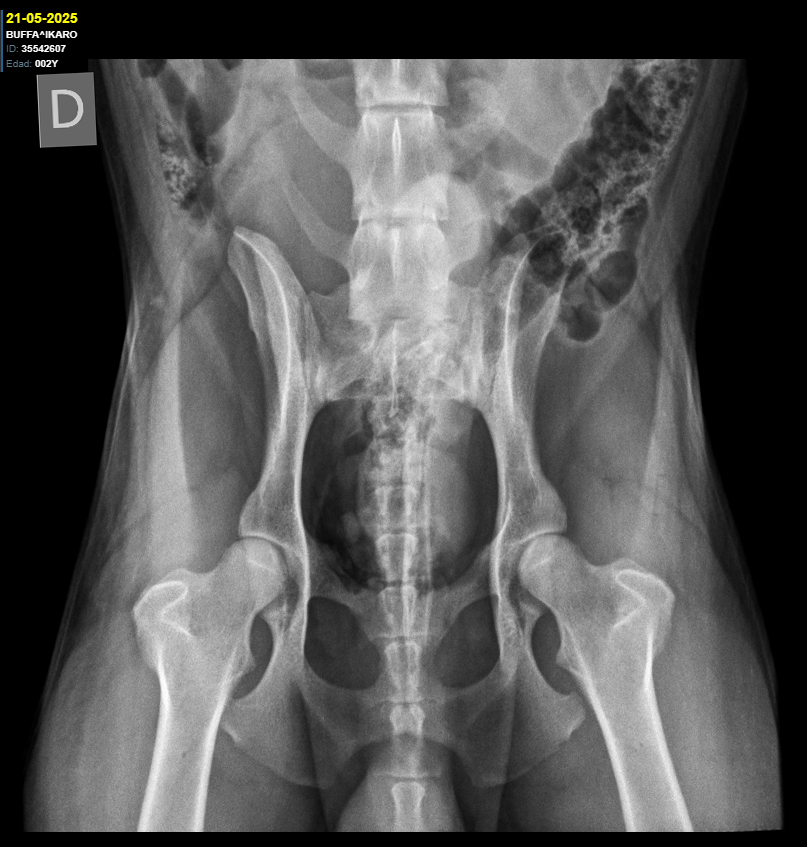

Cadera Codos:

HD A / ED 0/0

Cadera y Codos: